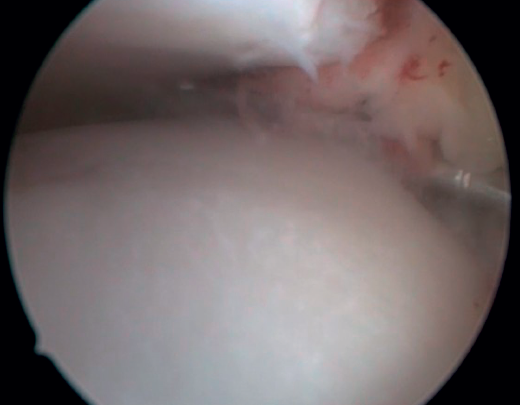

El PAT óseo por osteofitos también ha sido relacionado con la presencia de inestabilidad crónica. Se ha postulado que la alteración en la cinemática articular secundaria a la insuficiencia ligamentosa favorece el desarrollo de osteofitos en la región anterior de la tibia y el astrágalo(36,37). Estudios recientes han cuestionado la teoría de tracción capsular repetida como origen de los osteofitos en la práctica deportiva(38), ya que es fácilmente demostrable que los osteofitos se localizan intraarticulares por dentro de la inserción capsular, en el contexto de una artroscopia de tobillo (Figura 2). Por ello, la artroscopia con dorsiflexión de tobillo es fundamental para poder resecar los osteofitos de forma segura sin daño capsular ni a las estructuras suprayacentes, mientras que la técnica clásica de tracción (invasiva o no) dificultaría enormemente su resección, por lo que hoy en día se desaconseja su uso rutinario(3,39). Vega distingue dos tipos de osteofitos(3), según sean por trauma repetitivo (forma de pico) o por inestabilidad (en forma de visera). El concepto de microinestabilidad se asocia a microtraumatismos de repetición que podrían ser el origen de osteofitos con esta morfología característica (Figura 3).

La resección de osteofitos se realiza deslizándose desde su parte superior, rebajando gradualmente hasta alcanzar la zona articular (Figura 2). Con una pinza de tipo basket se puede resecar la zona más cercana a la articulación (Figura 5). Suele ser útil intercambiar los portales de visión y trabajo para visualizar y resecar completamente los osteofitos. Para el pinzamiento de partes blandas, un sinoviotomo de 3,8 o 4 mm suele ser suficiente. El vaporizador es útil en pinzamientos compactos, típicos de condiciones postraumáticas o reintervenciones, también para delimitar la parte ósea del osteofito antes de su resección.

Figura 2. Osteofito anterior de la tibia. A: en dorsiflexión la cápsula se separa del osteofito permitiendo su resección (B) mediante fresado.